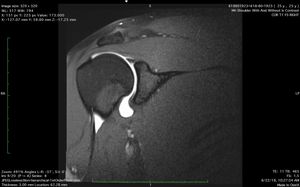

MRI Artgrogram

Arthrogram of right shoulder. What do you see?

Shoulder

Arthrogram

Mriarthrogram